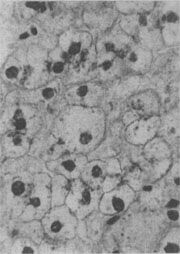

肾近曲小管上皮细胞玻璃样小滴变

图1-21 肾近曲小管上皮细胞玻璃样小滴变

上皮细胞胞浆内出现大小不等的均质圆形小滴